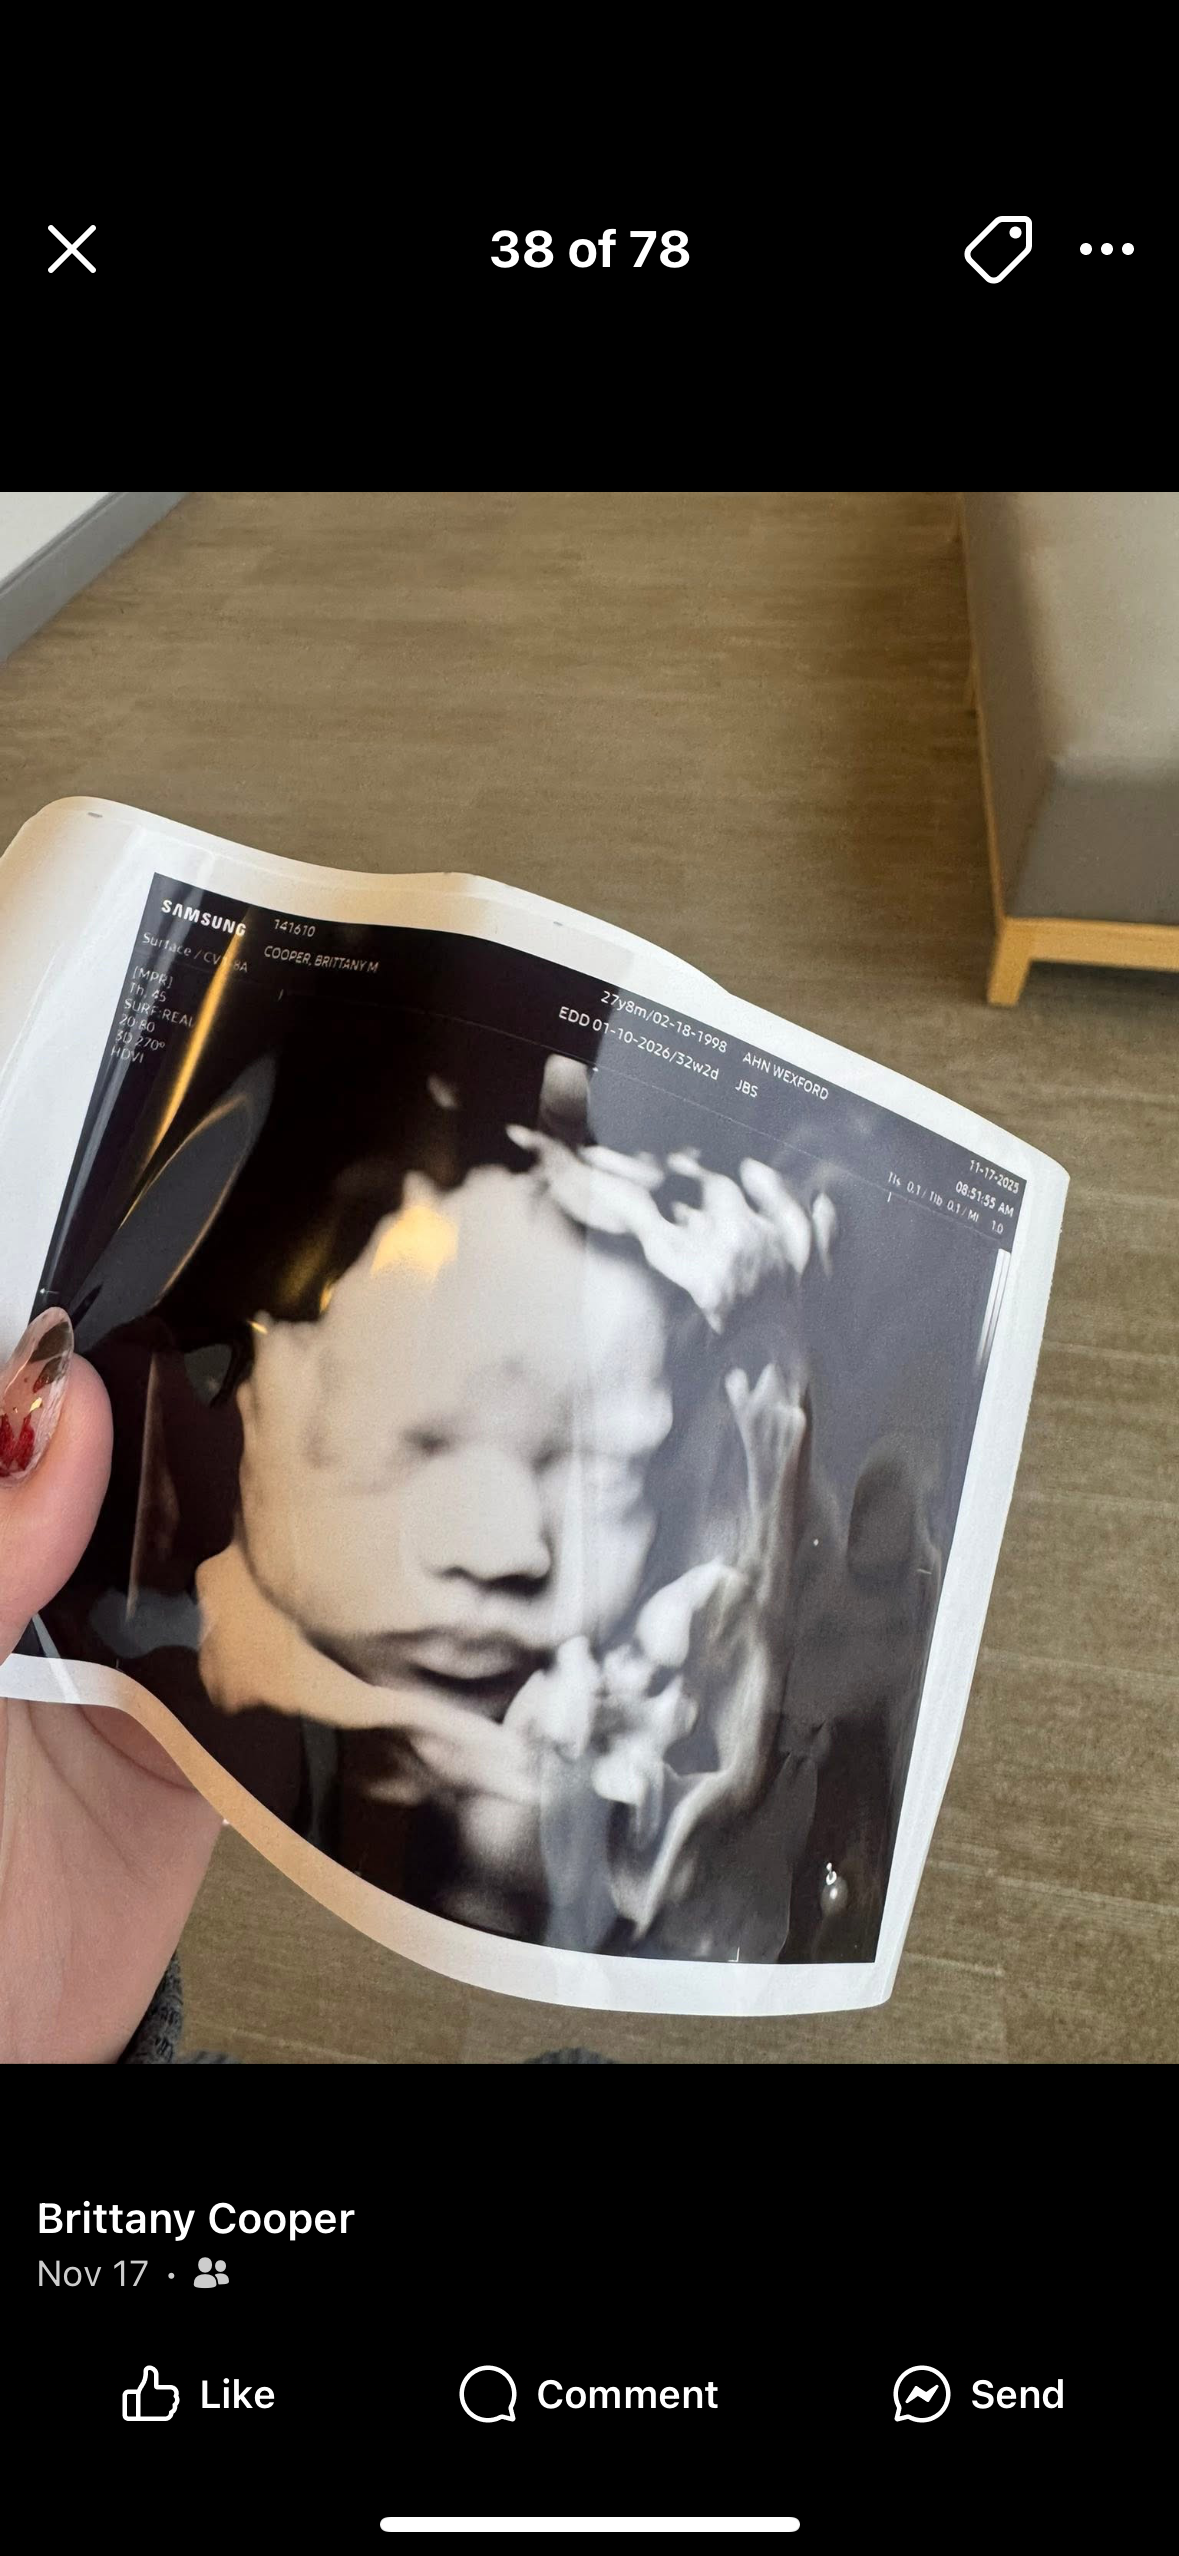

Hi, my name is Mary, but I am setting this GoFundMe up for Sean and Brittany Cooper. Approximately one month ago, Sean was involved in a motorcycle accident and is currently unable to work, unable to walk, and is soon undergoing rigorous physical therapy. Sean and Brittany currently have two beautiful boys, with a sweet baby girl on the way, due in January.